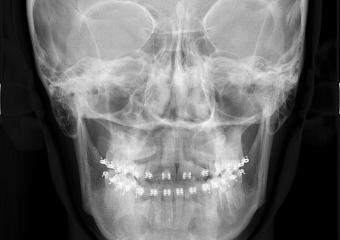

Telerradiografia frontal inicial  - Clínica Cliniface

Telerradiografia frontal inicial